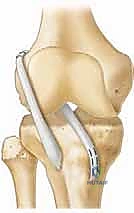

شكل 4: تحديد مسار النفق العظمي بدقة متناهية تحت توجيه الأشعة لضمان بقائه بعيداً عن صفيحة النمو الحساسة.

2. التقنية العابرة لصفائح النمو جزئياً (Partial Transphyseal)

تُستخدم للمراهقين في بداية البلوغ (12-14 سنة)، حيث اقتربوا من اكتمال النمو ولكن لا يزال هناك خطر.

* كيف تتم؟ يتم حفر نفق صغير وعمودي (لتقليل مساحة الاحتكاك بصفيحة النمو) في عظم الساق، بينما يتم تجنب صفيحة النمو في عظم الفخذ تماماً. يتم استخدام أوتار المأبض (Hamstrings) كطعم ناعم لا يحتوي على سدادات عظمية قد تلتحم وتوقف النمو.